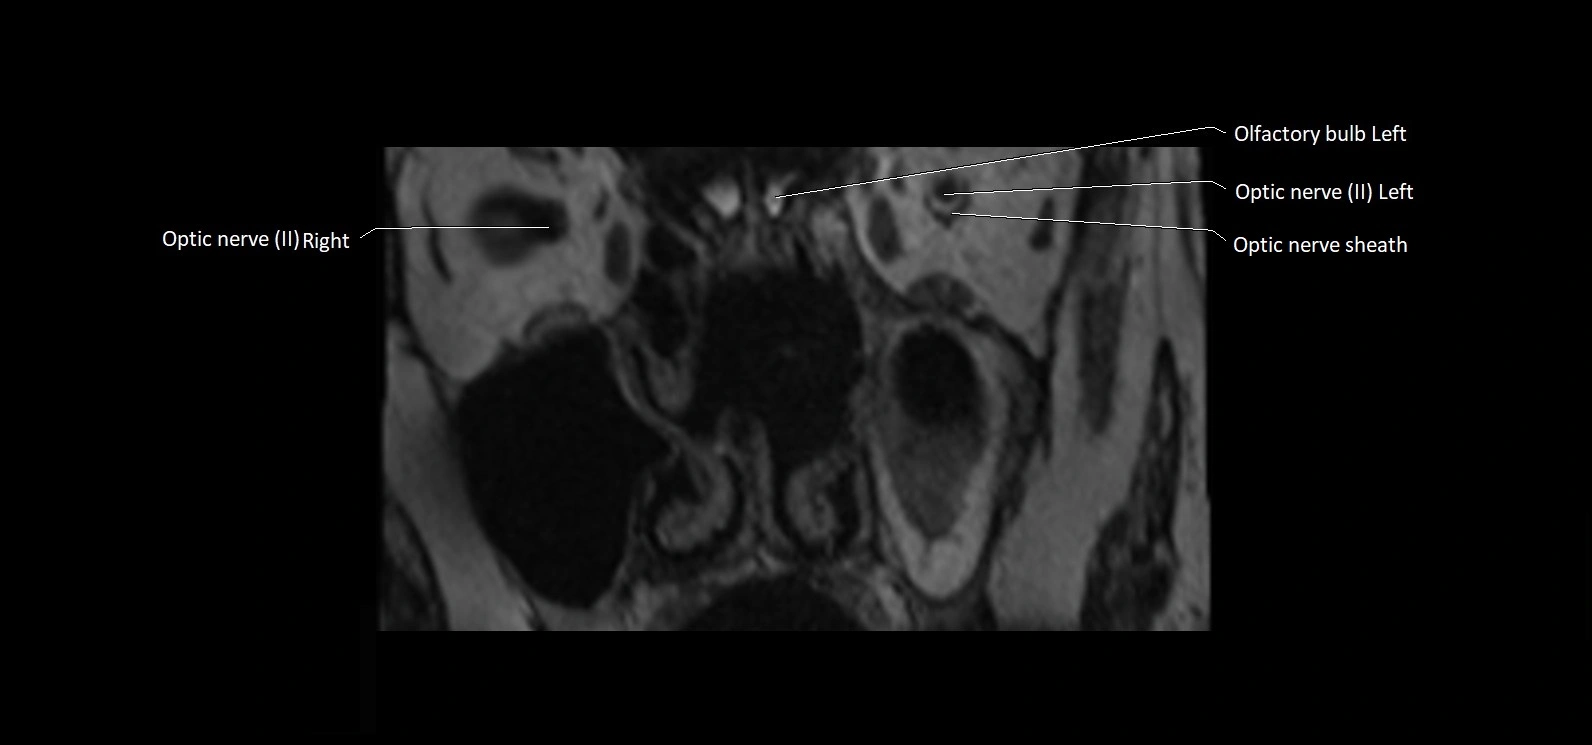

MRI images

image